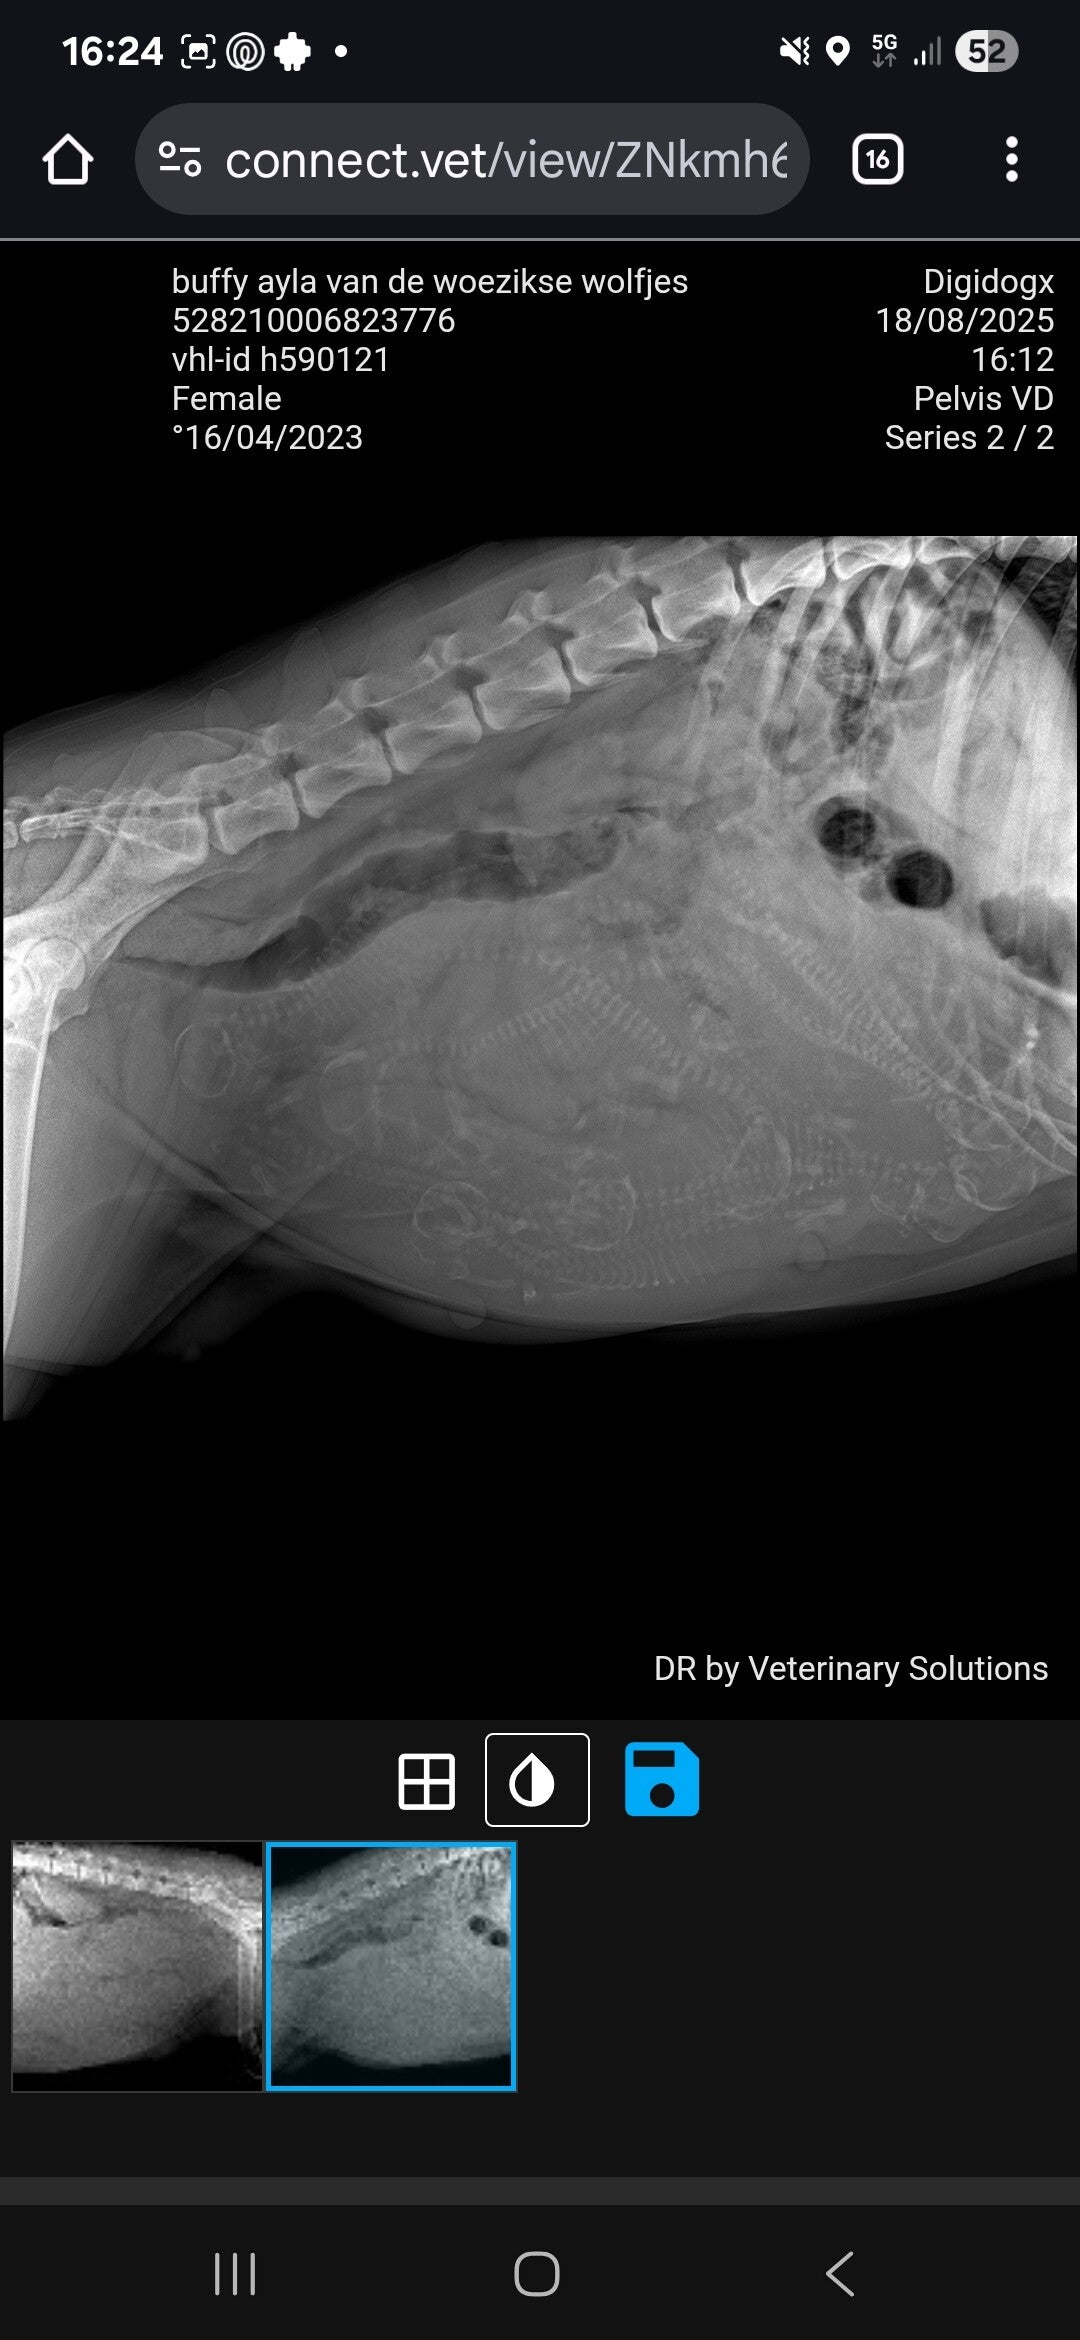

Op dag 52 van de dracht hebben we toch een röntgenfoto laten maken, zo benieuwd hoeveel pups we zouden kunnen tellen.

En jahoor een heel mooi buikje vol pups lieten zich snel al zien. 8 a 9 pups denken we samen geteld te hebben de dierenarts en ik. Nu genieten we nog van de dagen en hopen we op een voorspoedige bevalling.πŸ€πŸ₯°